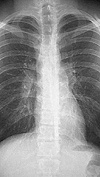

Диагностика в пневмологии направлена на активную профилактику, своевременное выявление и верификацию патологии бронхов, трахеи, плевры, легких, средостения, диафрагмы и грудной клетки. Диагностика заболеваний в пневмологии основана на анамнестических данных, результатах физических, клинических, лабораторных, рентгенологических, рентгенологических, эндоскопических, функциональных, ультразвуковых исследований и исследования. Отдельной областью диагностики в пневмологии является проведение скрининговых программ для выявления социально значимых заболеваний легких - туберкулеза и рака легких на ранних стадиях.